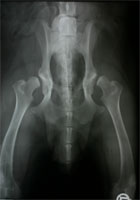

Sechs Wochen postoperativ wird der Hund erneut einer Lahmheitsuntersuchung unterzogen und das Fortschreiten der knöchernen Fusion durch eine Röntgenuntersuchung in tiefer Sedation beurteilt. Gegebenenfalls wird zu diesem Zeitpunkt die zweite Seite operiert (Abb 15). Es zeigt sich in der Regel eine deutliche Kallusbildung an der Osteotomiestelle des Os ilium. Die Manipulation der Articulatio coxae sollte einen guten Grad von Beweglichkeit ergeben. In den besonderen Fällen, bei denen eine 40°-Platte eingesetzt wurde, kann die Abduktion und Extension des Hüftgelenkes ein wenig eingeschränkt sein. Ab Woche 6 sollte mit einem aktiven aufbauenden Bewegungstraining begonnen werden. Auf den besonderen Wert eine Physiotherapie braucht nicht hingewiesen zu werden.

DBO Kontrollröntgen nach 6 Monaten

Abbildung 15: Kontrolle nach 6 Wochen zeigt die Fusion des Os ilium auf der linken Bildseite. Die zweite Seite ist frisch umgestellt.

In Studien, die sich über einen Zeitraum von 8 Jahren erstreckten, zeigten 76 % der DBO-Operierten noch ein exzellentes Ergebnis ohne Coxarthrose mit uneingeschränkter Beweglichkeit und völliger Schmerzfreiheit (Abb. 16). Bei dem Rest der Patienten zeigten sich röntgenologisch leichte Arthroseerscheinungen, die klinisch jedoch zu keiner Einschränkung der Bewegung führten und in der Regel auch keine Gabe von Schmerzmitteln erforderten.

DBO arthrosefreies Hüftgelenk nach 8 Jahren

Abbildung 16: Arthrosefreies Hüftgelenk, welches acht Jahre zuvor mit einer Dreifachen Beckenosteotomie stabilisiert wurde.

DBO bilateral Ausheilungsergebnis

Abbildung 17: Ausheilungsergebnis einer bilateralen Dreifachen Beckenosteotomie. Die bisweilen ausbleibende Fusion des Os ischium ist klinisch bedeutungslos.

Die Dreifache Beckenosteotomie (DBO) beseitigt nicht nur die Lockerheit des dysplastischen Hüftgelenkes sondern führt zu einem festen und tiefen Sitz des Caput ossis femoris im Acetabulum. Die tragende und belastete Gelenkfläche wird durch die Umstellung verdreifacht bis vervierfacht. Dies führt den Stress auf den Gelenkknorpel in physiologische Dimensionen zurück. Im Idealfall sind im weiteren Verlauf keinerlei röntgenologische Anzeichen einer Coxarthrose zu verzeichnen (Abb. 17). Treten sie bei operierten Patienten mit schwersten HD Graden später dennoch auf, so sind sie von der Form her milde und von keiner Lahmheitssymptomatik begleitet. 92 % der Patienten sind nach spätestens 7 Monaten völlig lahmheitsfrei. Langzeitstudien beweisen, dass die Hunde im Laufe ihres Lebens klinisch fast immer beschwerdefrei sind und selbst im Alter weder antiphlogistische Medikamente noch neuerlicher chirurgischer Interventionen bedürfen. Es wäre wünschenswert, wenn die Tierbesitzer dysplastischer Junghunde mehr über die Chancen und Möglichkeiten informiert würden, die die Dreifache Beckenosteotomie eröffnet. Sie ist bei korrekter Indikationsstellung sowie Erfahrung der Operateure der Goldstandard in der Therapie der juvenilen Hüftgelenksdysplasie und ein Jahrzehnte lang international erprobtes und bewährtes Verfahren.